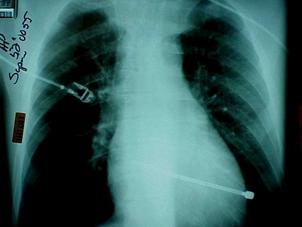

Pneumotorace sufocant bilateral Pneumotorace sufocant stang

Pneumotorace

sufocant stang Pneumotorace

sufocant drept Pneumotorace

sufocant drept